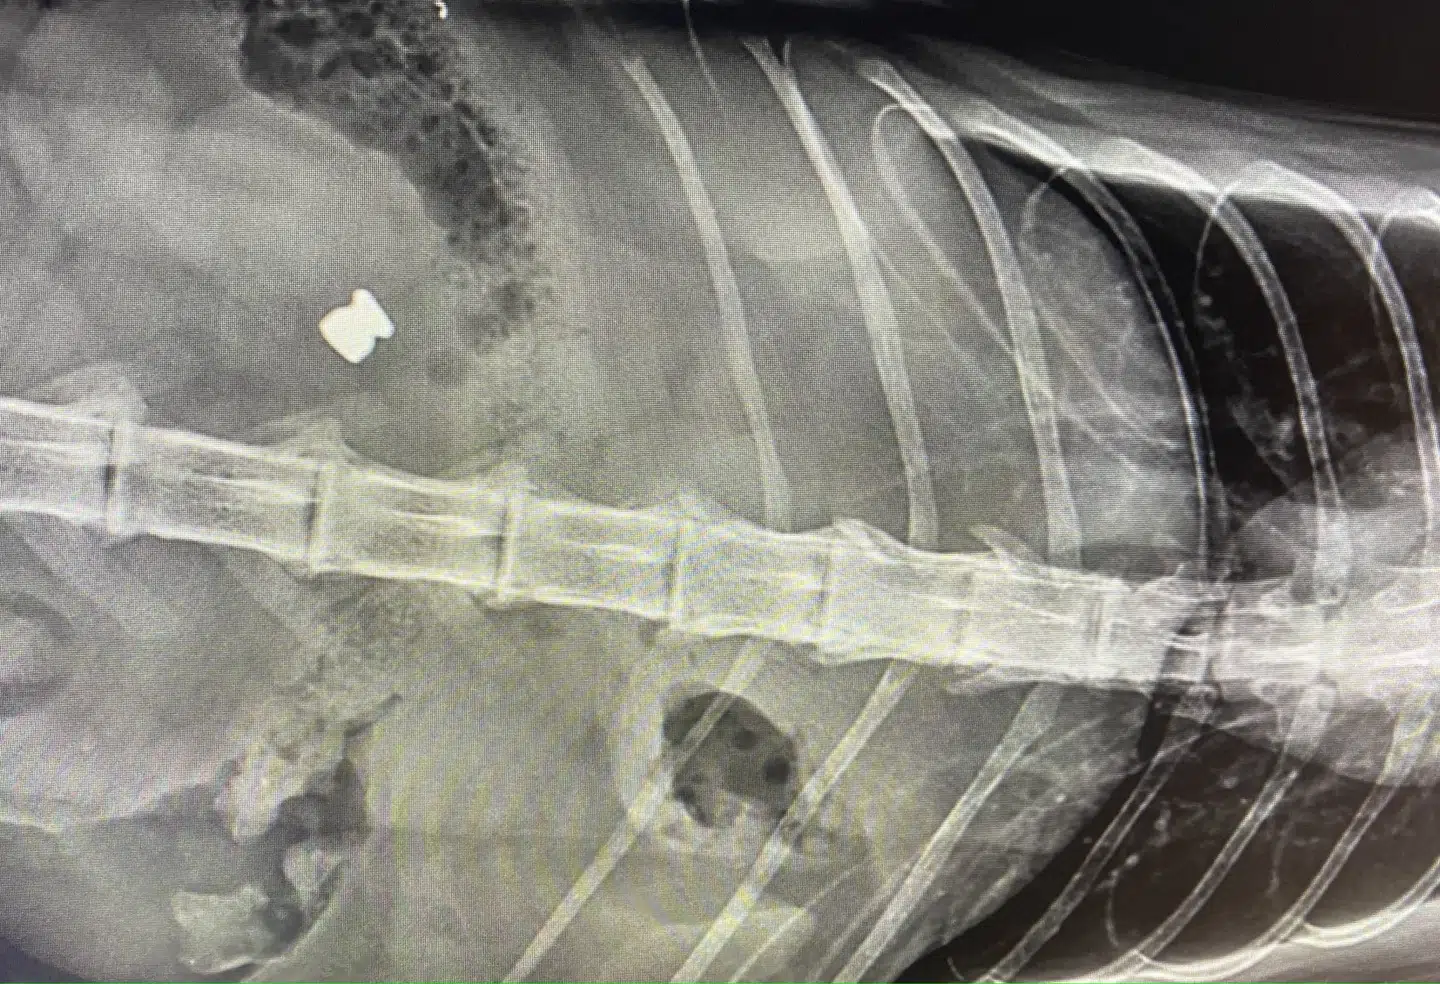

Derfor blev der taget røntgenbilleder af kattens indre, og her fandt dyrlægen et fremmedlegeme.

»Et hagl. Nogen havde skudt katten med et luftgevær!,« skriver Dyrlægerne Ved Stranden og fortsætter: